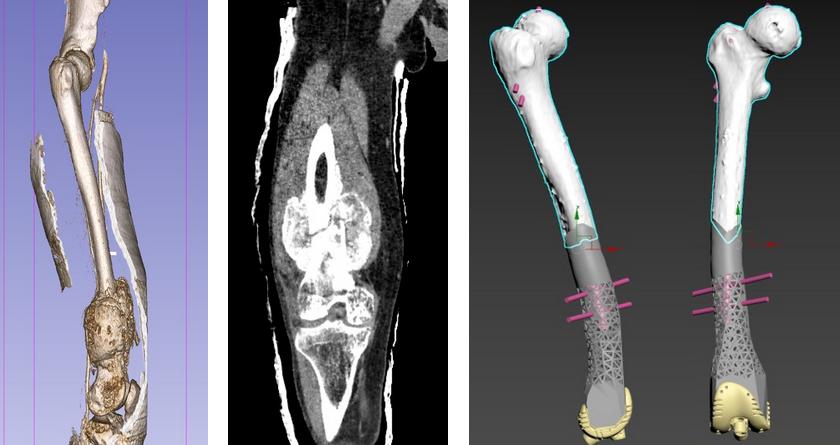

Етапи проектування онкопротезування? Хворий Г.58 остеосаркома стегнової кістки